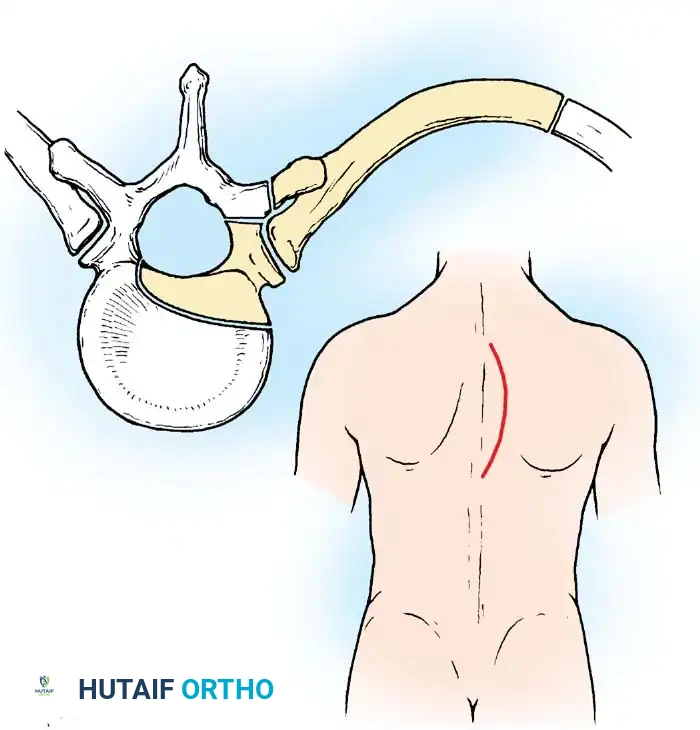

The surgical approach to the tuberculous spine is dictated entirely by the anatomic level of the lesion. The goal is to achieve direct, unhindered access to the anterior vertebral bodies to facilitate complete evacuation of the cold abscess, radical corpectomy of the diseased segments, and precise placement of a structural strut graft.

TECHNIQUE 40-12: DORSOLATERAL APPROACH TO THE DORSAL SPINE (ROAF ET AL.)

While the anterior approach is the gold standard, the dorsolateral approach is a highly effective alternative for the thoracic spine when a formal thoracotomy is contraindicated (e.g., severe pulmonary compromise) or when posterior drainage of a massive abscess is preferred.

- Neural Identification: Identify two (preferably three) intercostal nerves. Trace them medially into the intervertebral foramina. These nerves serve as critical anatomic landmarks, indicating the exact level of the spinal cord within the canal.